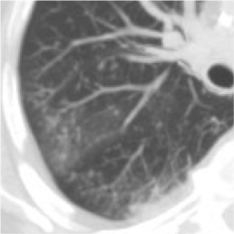

E). A. INVASIVA DE LA VÍA AÉREA:

Aspergillus afectando la membrana basal de la vía aérea.

Clínica: Pacientes neutropénicos con traqueobronquitis, bronquiolitis, bronconeumonía.

Hallazgos radiológicos: La placa simple puede ser normal o presentar engrosamiento bronquial y traqueal. En el TAC: En la bronquiolitis, vemos microndódulos centrolobulillares con ramificaciones lineales dando patrón en árbol en brote de distribución parcheada (Diagnóstico diferencial con TBC, MAI, mycoplasma). En la bronconeumonía, consolidaciones peribronquiales (hallazgo inespecífico).